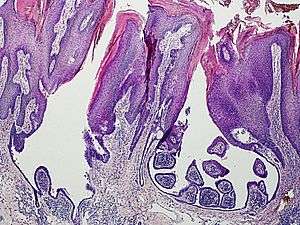

An example of a syringocystadenoma papilliferum

Syringocystadenoma papilliferum (also known as "Syringadenoma papilliferum") is an apocrine tumor.[1]